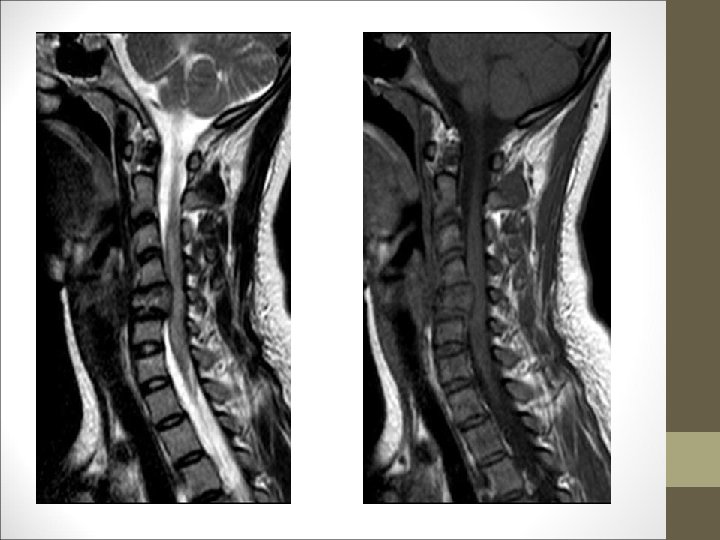

TC Desplazamientos de fragmentos óseos ¿Algo mas? Desplazamientos discales y lesiones ligamentosa FACULTAD DE MEDICINA DEPARTAMENTO DE CIRUGÍA NEUROCIRUGÍA RM